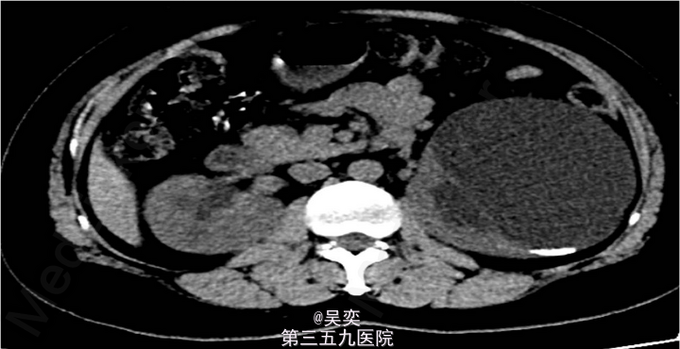

3、查体:无阳性体征 4、辅助检查:我院泌尿系B超:右输尿管上段结石并上段扩张,双肾多发结石。入院后白细胞总数10.550x10E9/L,中性粒细胞绝对值6.970x10E9/L。尿常规:白细胞计数50.30个/ul,红细胞计数145.70个/ul。生化全套:谷丙转氨酶75.000U/L,谷草转氨酶44.000U/L。双肾CTU:1、左肾盂和中下盏铸型结石较前稍增多,左肾中度积水。2、右肾多发结石,右肾中度积水,右侧输尿管上段炎症。3、左肾上极巨大囊性病变较前增大,考虑扩张的肾盏,内有结石。4、盆腔多发静脉石。5、前列腺小钙化灶。其余术前常规抽血结果无特殊。

5、诊断:肾积水伴输尿管结石,肾结石,精神分裂症 6、入院后完善相关检查,心电图、胸片未见异常,CT示:1、左肾盂和中下盏铸型结石较前稍增多,左肾中度积水。2、右肾多发结石,右肾中度积水,右侧输尿管上段炎症。3、左肾上极巨大囊性病变较前增大,考虑扩张的肾盏,内有结石,排除手术禁忌症,经术前准备,于左侧经皮肾镜碎石取石术,手术顺利,术后恢复较好。